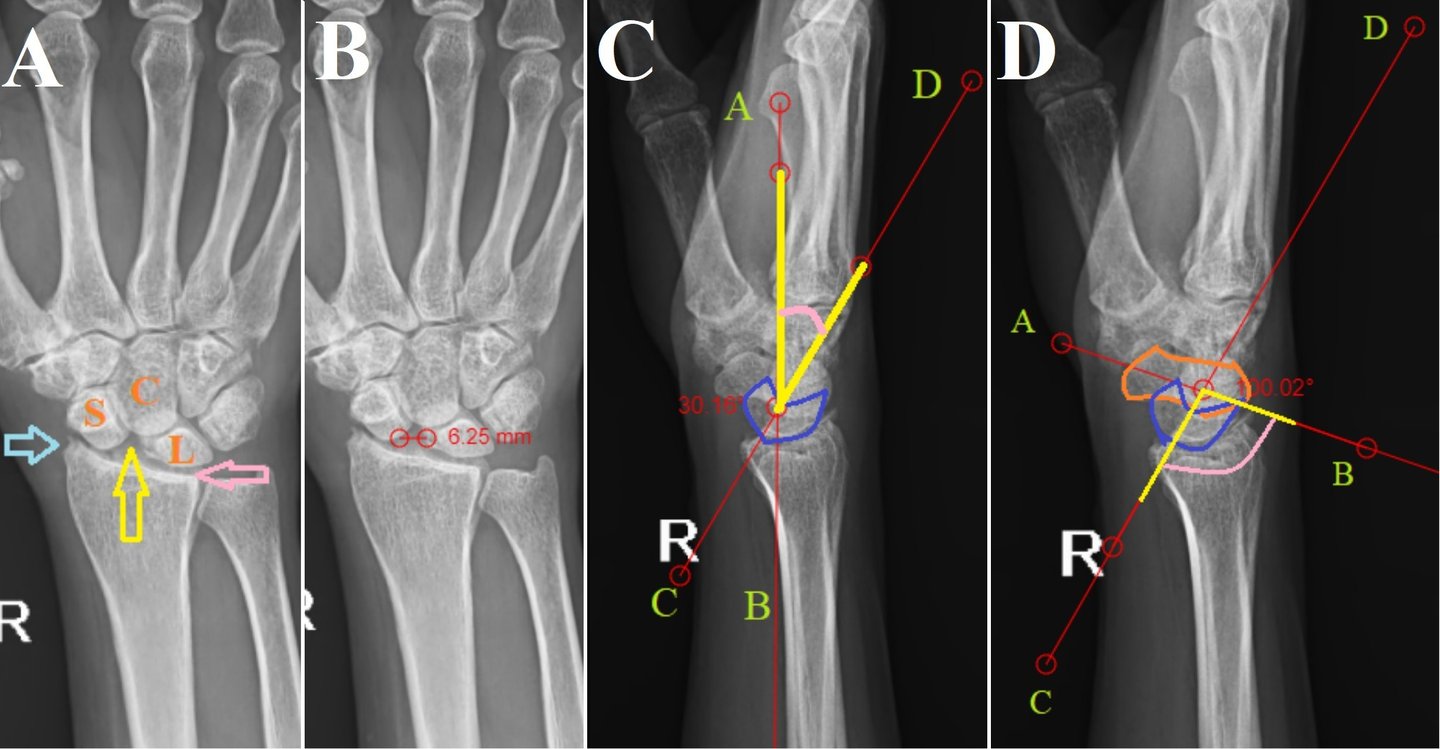

Scapholunate Advanced Collapse Wrist - Keeping it Simple

Scapholunate advanced collapse is a rare condition of progressive deformity, instability, and arthritis that affects the radiocarpal and mid-carpal joints of the wrist. It occurs as a result of injury to the scapholunate ligament being left untreated. A complete in-depth radiological analysis can demonstrate several signs that can prevent missed diagnosis. Increased awareness regarding these radiological signs can avoid the unnecessary higher imaging modalities being performed.

Isolated lunate dislocation

Perilunate dislocations are rare traumatic injuries of the wrist. They are classified according to the Mayfield classification system. Among these, lunate dislocations represent only the type IV injury, which are among the most unstable. Isolated lunate dislocations are often unrecognised as the rest of the carpus remains aligned. The rate of incorrect diagnosis is reported to be as high as 25%. Neglected lunate dislocations can lead to median nerve dysfunction, carpal instability, avascular necrosis of lunate and arthritis. Careful analysis of radiographs is required for diagnosis, indicated by disruptions of Gilula’s arc, lunocapitate overlap on posteroanterior radiographs and spilling teacup sign, increased radiolunate angle on lateral radiographs.